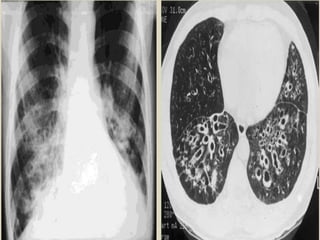

 Signs on CXR include the identification of

parallel linear densities, tram-track opacities, or

ring shadows reflecting thickened and

abnormally dilated bronchial walls. These

bronchial abnormalities form a spectrum from

subtle or barely perceptible 5-mm ring

shadows to obvious cysts. Tubular branching

opacities conforming to the expected bronchial

branching pattern may result from fluid or

mucous filling of bronchi

 Signs onCXR include the identification of parallel linear densities, tram-track opacities, or ring shadows reflecting thickened and abnormally dilated bronchial walls. These bronchial abnormalities form a spectrum from subtle or barely perceptible 5-mm ring shadows to obvious cysts. Tubular branching opacities conforming to the expected bronchial branching pattern may result from fluid or mucous filling of bronchi